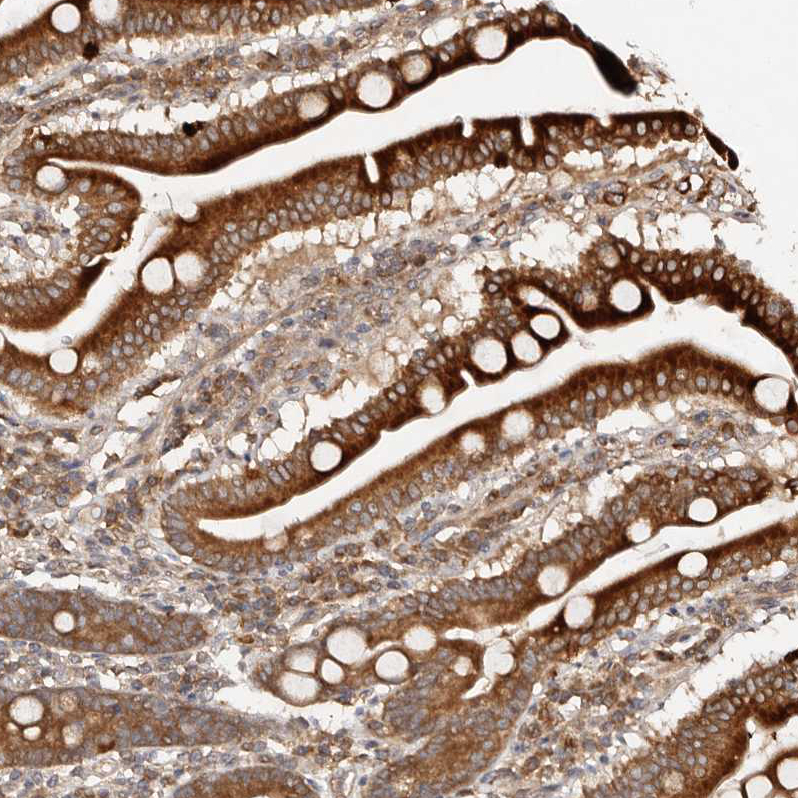

Immunohistochemical staining of human lung shows moderate cytoplasmic positivity in macrophages.